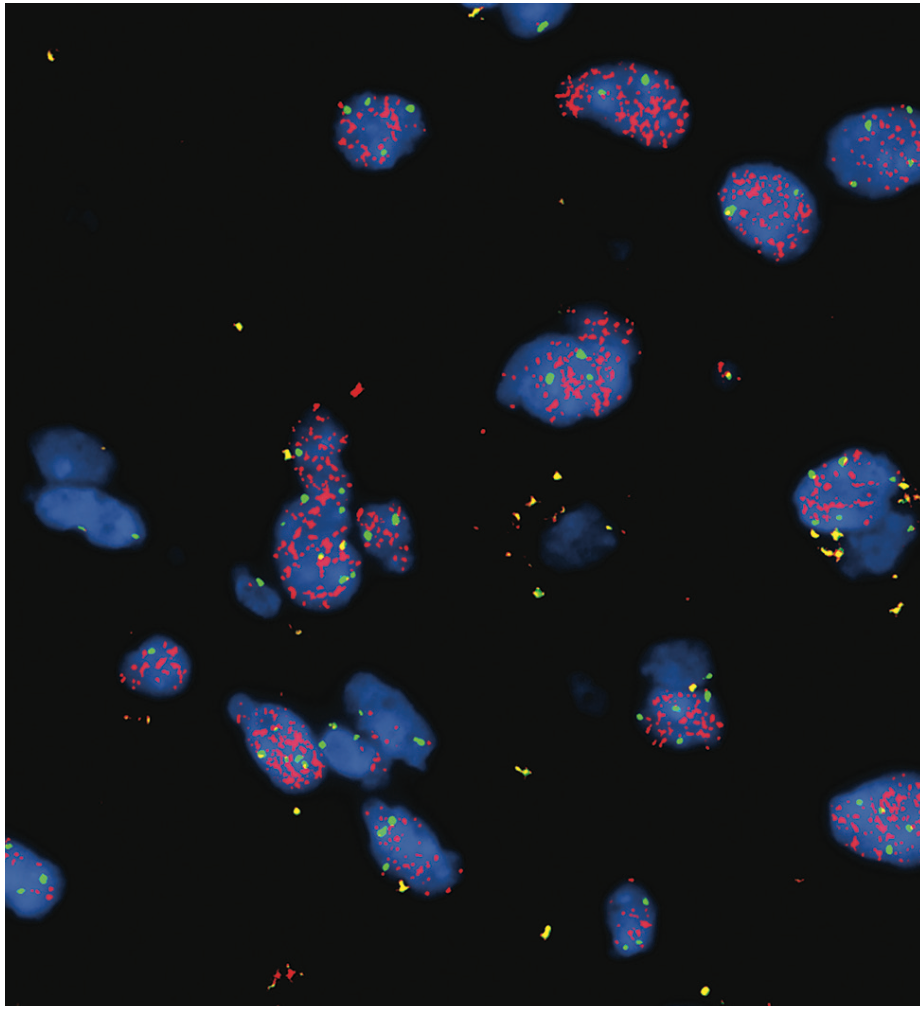

Hematoxylin and eosin staining of the surgical specimen demonstrated mildly hypercellular atypical glial cells without evidence of increased mitotic figures or necrosis (Figure 2A). Ki-67 labeling index was low, approximately 1% (Figure 2B). Immunohistochemistry for IDH1 R132H was negative. Next-generation sequencing (NGS) was performed for further characterization, revealing the following key findings: TERT c.-146C> T mutation with 26% allele frequency, EGFR amplification with an estimated copy number of 158 (confirmed by fluorescence in situ hybridization with an EGFR signal/control signal ratio of 7.6; see Figure 3), and CDKN2A deletion. National Institutes of Health methylation profiling was performed, which indicated a consensus match to glioblastoma, IDH wild-type, with a high confidence score. This was supported by the presence of the +7/–10 chromosomal copy number change, TERT promoter mutation, and the high-level EGFR amplification, confirming that the neoplasm exhibited the molecular features of glioblastoma. O6-methylguanine-DNA methyltransferase (MGMT) promoter methylation analysis showed negative methylation status.

FIGURE 3. Fluorescence in Situ Hybridization With EGFR Signal/Control